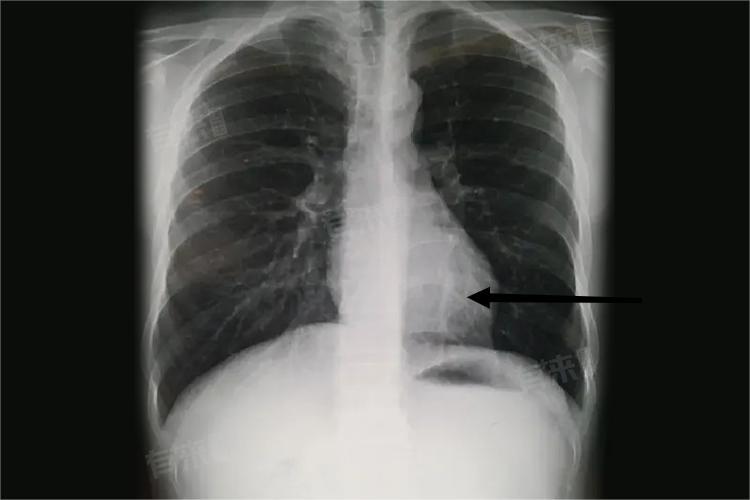

3、慢性阻塞性肺疾病:

长期的气道阻塞,如慢性支气管炎、肺气肿,使肺内气体潴留。肺泡过度膨胀,对胸廓产生持续压力,胸廓为适应这种压力而逐渐变形,前后径增大,形成桶状胸,随着病情发展,桶状胸会愈发明显。